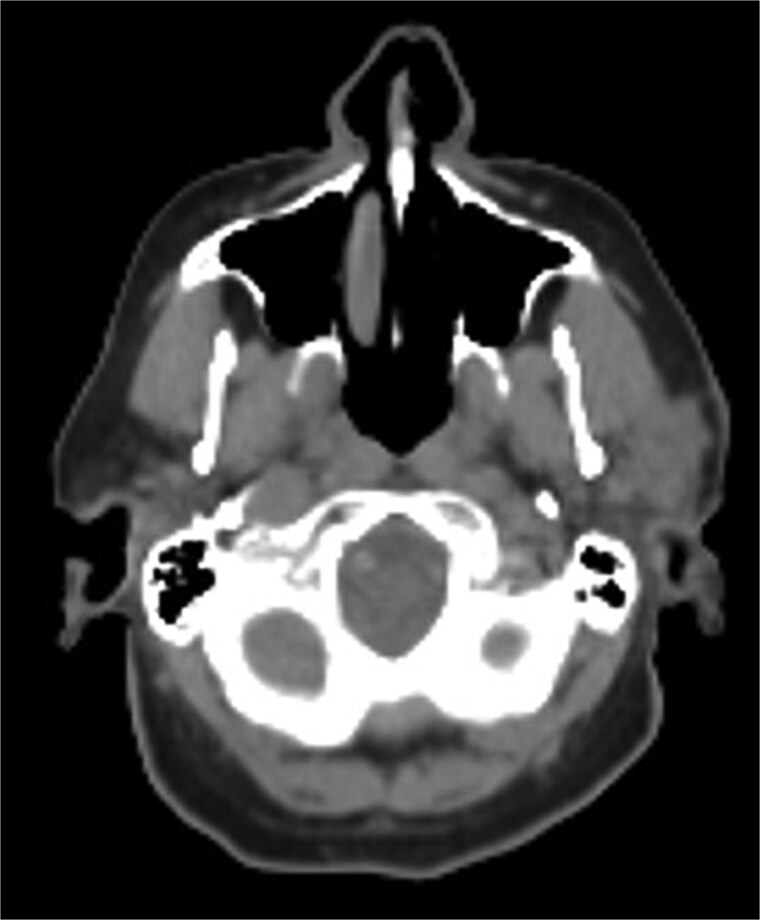

腮腺的同步鳞状细胞癌(SCC)和慢性淋巴细胞白血病(CLL)是罕见的,个性化治疗的证据有限。我们报告一位75岁男性既往皮肤鳞状细胞癌,表现为高代谢腮腺肿块和颈部淋巴结病;细针穿刺证实SCC。手术显示多发淋巴结低分化SCC和CLL。他接受了放疗,但出现了局部SCC复发,没有全身CLL症状。耳部复发需要广泛的手术切除和重建。遗传谱显示高肿瘤突变负担(bbb50突变/Mb)和ARID1B、CDKN2A、MSH2、PMS2和TP53突变。他接受了6个周期的西妥昔单抗治疗,随后是基于循环DNA水平上升的西妥昔单抗靶向治疗。本病例强调了遗传谱和TMB、FISH和免疫组织化学等工具在管理晚期或复杂腮腺恶性肿瘤(包括同步SCC和CLL)的风险分层和个性化治疗中的价值,以优化患者的预后。

Synchronous squamous cell carcinoma (SCC) and chronic lymphocytic leukemia (CLL) in the parotid gland is rare, with limited evidence on personalized treatment. We report a 75-year-old male with prior cutaneous SCC who presented with a hypermetabolic parotid mass and cervical lymphadenopathy; fine needle aspiration confirmed SCC. Surgery revealed poorly differentiated SCC and CLL in multiple lymph nodes. He underwent radiotherapy but developed regional SCC relapse without systemic CLL symptoms. Recurrence in the ear required extensive surgical resection and reconstruction. Genetic profiling showed high tumor mutational burden (>50 mutations/Mb) and mutations in ARID1B, CDKN2A, MSH2, PMS2, and TP53. He received six cycles of cemiplimab followed by cetuximab-based targeted therapy, based on rising circulating DNA levels. This case emphasizes the value of genetic profiling and tools like TMB, FISH, and immunohistochemistry for risk stratification and personalized treatment in managing advanced or complex parotid malignancies, including synchronous SCC and CLL, to optimize patient outcomes.